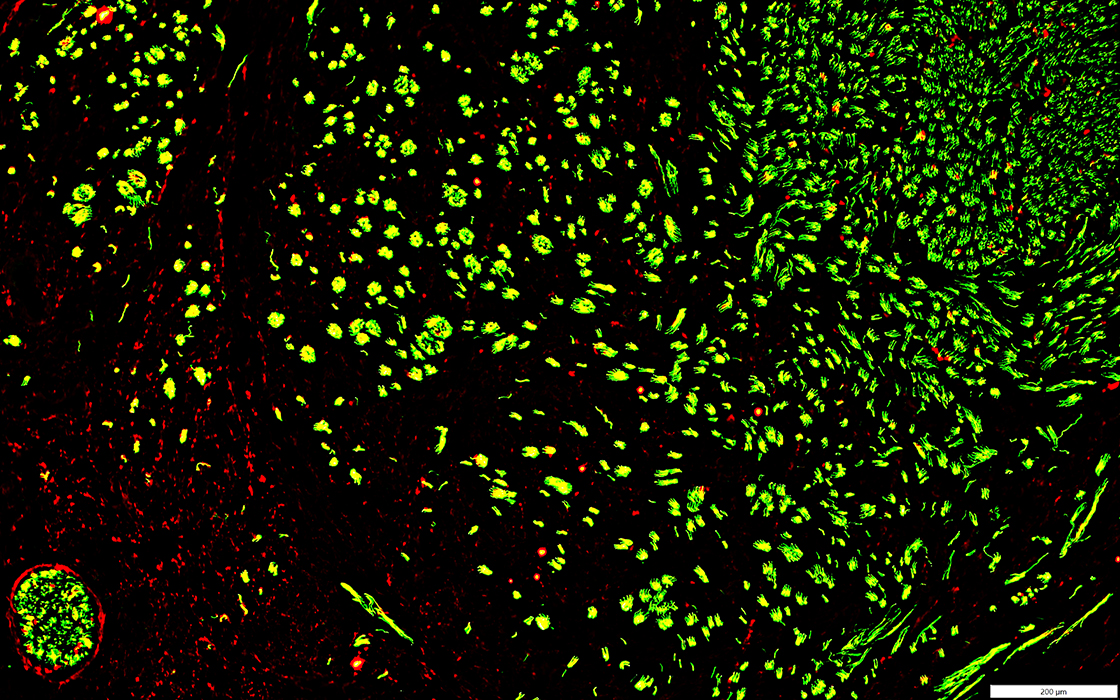

Neurofilament (Green); NCAM (Red)

NCAM

Present in Schwann cells around most axons in Neuroma (Left) & surrounding axon sprouts (Right)

Many have associated MBP+ Schwann cells (Yellow)

Neurofilament (Green); MBP (Red)